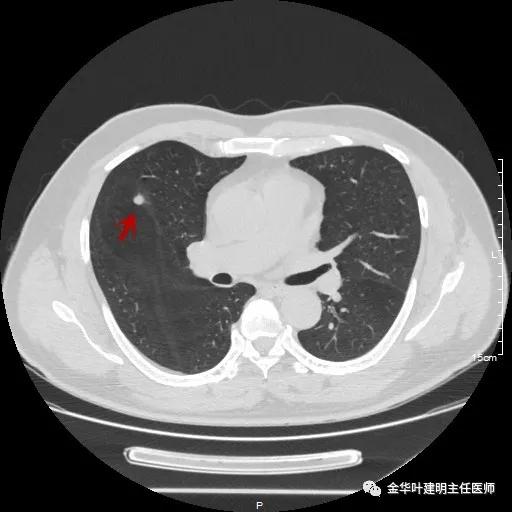

同样的地方,说明是同一病灶,但较1年前明显增大变圆,现在是圆形结节了,大小约在6-7毫米许,同样无明显磨玻璃成份,也无其他恶性征象,看着像肺内淋巴结或胶原增生结节或肉芽肿性结节。

其实分开看两年的片子都考虑是良性的,但问题是病灶进展增大了!该如何是好?另外内科接下来需行大剂量激素治疗,若为结核、若为真菌、若为肿瘤,大剂量激素会不会有影响?免疫抑制情况下,感染是不是要加重或扩散?真万一是肿瘤,是不是更可导致不良结果?此外,穿刺病灶太小太深,PET-CT有点小贵,而且这么小的结节,到底价值几何也难说。